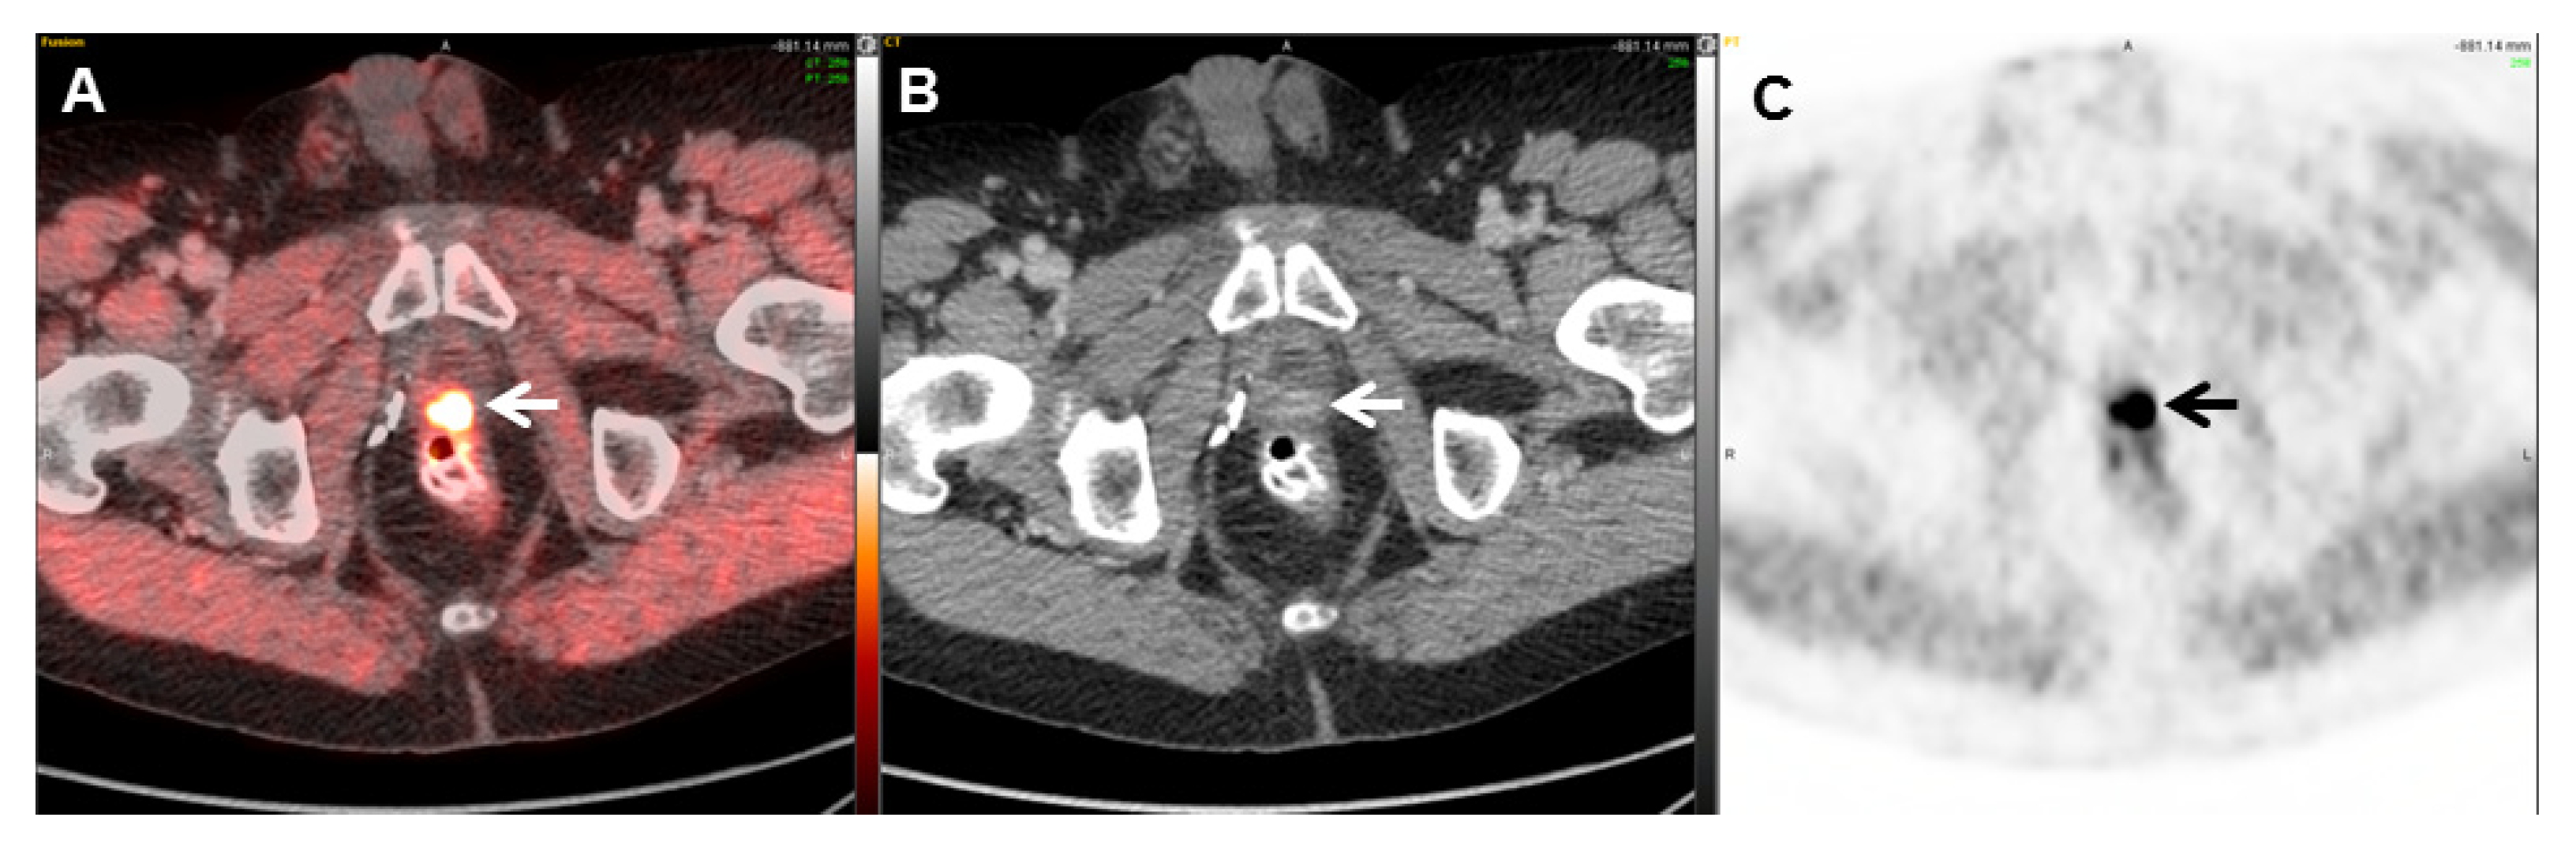

- Dietlein, M.; Kobe, C.; Kuhnert, G.; Stockter, S.; Fischer, T.; Schomacker, K.; Schmidt, M.; Dietlein, F.; Zlatopolskiy, B.D.; Krapf, P.; et al. Comparison of [18F]DCFPyL and [ 68Ga]Ga-PSMA-HBED-CC for PSMA-PET Imaging in Patients with Relapsed Prostate Cancer. Mol. Imaging Biol. 2015, 17, 575–584. [Google Scholar] [CrossRef]

- Pienta, K.J.; Gorin, M.A.; Rowe, S.P.; Carroll, P.R.; Pouliot, F.; Probst, S.; Saperstein, L.; Preston, M.A.; Alva, A.S.; Patnaik, A.; et al. A Phase 2/3 Prospective Multicenter Study of the Diagnostic Accuracy of Prostate Specific Membrane Antigen PET/CT with 18F-DCFPyL in Prostate Cancer Patients (OSPREY). J. Urol. 2021, 206, 52–61. [Google Scholar] [CrossRef]

- Morris, M.J.; Rowe, S.P.; Gorin, M.A.; Saperstein, L.; Pouliot, F.; Josephson, D.; Wong, J.Y.C.; Pantel, A.R.; Cho, S.Y.; Gage, K.L.; et al. Diagnostic Performance of 18F-DCFPyL-PET/CT in Men with Biochemically Recurrent Prostate Cancer: Results from the CONDOR Phase III, Multicenter Study. Clin. Cancer Res. Off. J. Am. Assoc. Cancer Res. 2021, 27, 3674–3682. [Google Scholar] [CrossRef]

- Keam, S.J. Piflufolastat F 18: Diagnostic First Approval. Mol. Diagn. Ther. 2021, 25, 647–656. [Google Scholar] [CrossRef]

- Ulaner, G.A.; Thomsen, B.; Bassett, J.; Torrey, R.; Cox, C.; Lin, K.; Patel, T.; Techasith, T.; Mauguen, A.; Rowe, S.P.; et al. 18F-DCFPyL PET/CT for Initially Diagnosed and Biochemically Recurrent Prostate Cancer: Prospective Trial with Pathologic Confirmation. Radiology 2022, 305, 419–428. [Google Scholar] [CrossRef]

- Rowe, S.P.; Macura, K.J.; Mena, E.; Blackford, A.L.; Nadal, R.; Antonarakis, E.S.; Eisenberger, M.; Carducci, M.; Fan, H.; Dannals, R.F.; et al. PSMA-Based [18F]DCFPyL PET/CT Is Superior to Conventional Imaging for Lesion Detection in Patients with Metastatic Prostate Cancer. Mol. Imaging Biol. 2016, 18, 411–419. [Google Scholar] [CrossRef] [PubMed]